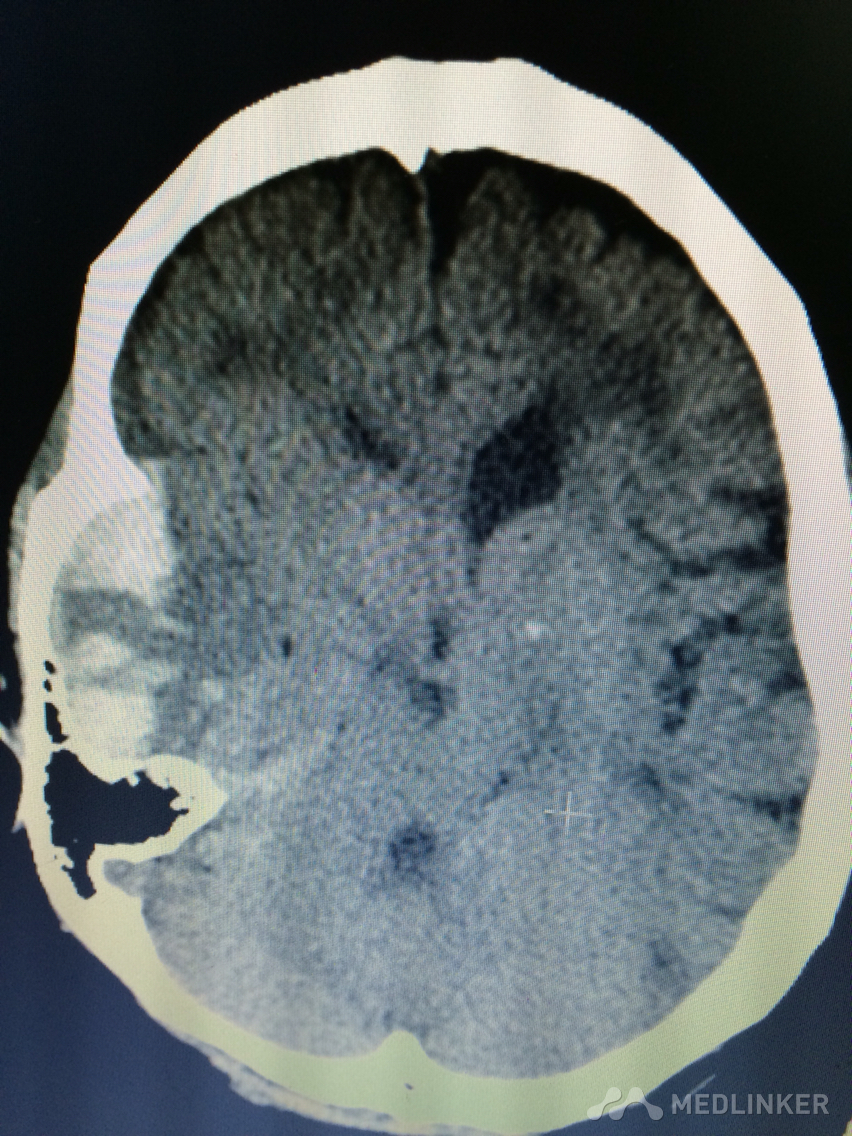

下面的CT考虑?

1天前,患者睡醒后出现反应迟钝,认知功能障碍,左侧肢体乏力。 既往无高血压病史,近期无外伤史。